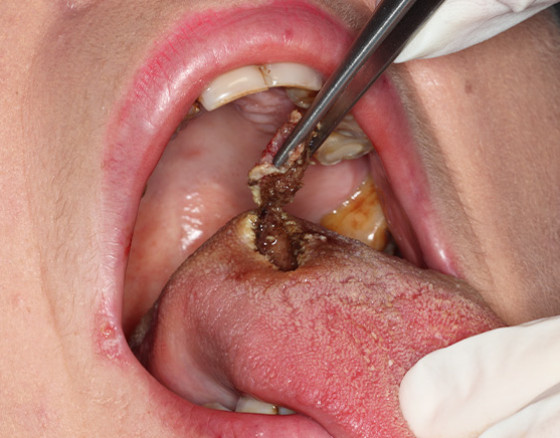

A paciente apresentou-se na nossa clínica para uma consulta de check up e rotina, tendo o médico observado uma lesão na língua. Macroscopicamente identificou-se uma lesão ulcerosa dorsal na língua, apresentando características de malignidade.

Após reavaliação médica e findo o tratamento de espera, a evolução foi pouco positiva, a lesão mantinha-se idêntica. Observa-se uma ulceração de cor avermelhada e endurecida nas bordas e áreas subjacentes. A opção seria, então, encaminhar para a especialidade de cirurgia para biópsia.

A biópsia foi realizada na Medway pelo médico cirurgião Dr. João Faria em conjunto com a Dra. Maria Inês Mateus e o Dr. Daniel Silva.